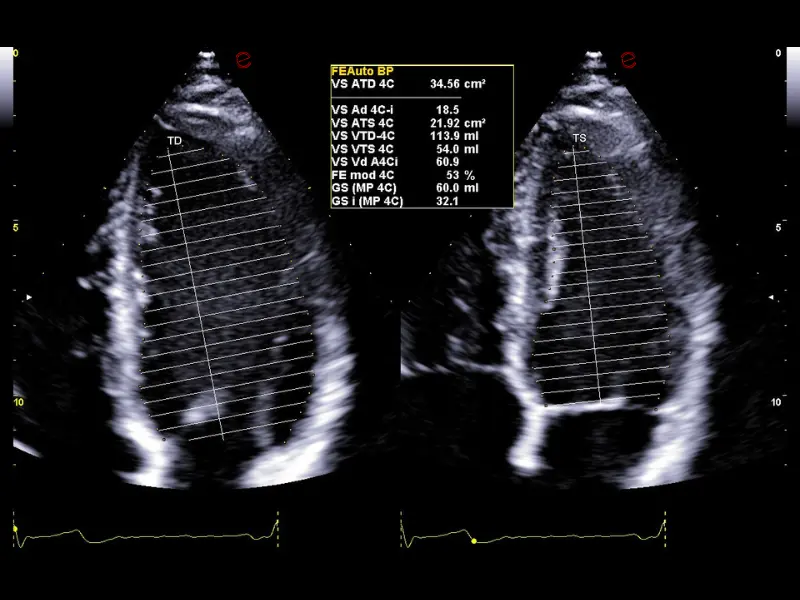

MyLab™C30 - FE

MyLab™C30 - FE